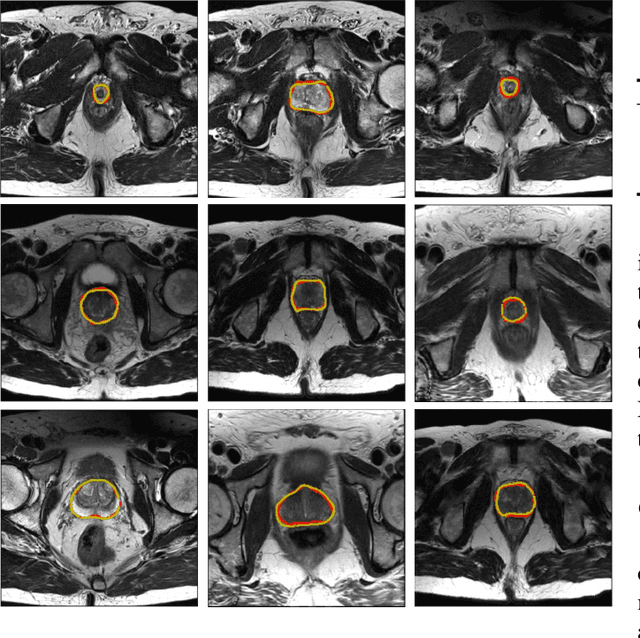

Abstract:Medical image segmentation is a fundamental task in medical image analysis. Despite that deep convolutional neural networks have gained stellar performance in this challenging task, they typically rely on large labeled datasets, which have limited their extension to customized applications. By revisiting the superiority of atlas based segmentation methods, we present a new framework of One-pass aligned Atlas Set for Images Segmentation (OASIS). To address the problem of time-consuming iterative image registration used for atlas warping, the proposed method takes advantage of the power of deep learning to achieve one-pass image registration. In addition, by applying label constraint, OASIS also makes the registration process to be focused on the regions to be segmented for improving the performance of segmentation. Furthermore, instead of using image based similarity for label fusion, which can be distracted by the large background areas, we propose a novel strategy to compute the label similarity based weights for label fusion. Our experimental results on the challenging task of prostate MR image segmentation demonstrate that OASIS is able to significantly increase the segmentation performance compared to other state-of-the-art methods.

Abstract:Accurate segmentation of the prostate from magnetic resonance (MR) images provides useful information for prostate cancer diagnosis and treatment. However, automated prostate segmentation from 3D MR images still faces several challenges. For instance, a lack of clear edge between the prostate and other anatomical structures makes it challenging to accurately extract the boundaries. The complex background texture and large variation in size, shape and intensity distribution of the prostate itself make segmentation even further complicated. With deep learning, especially convolutional neural networks (CNNs), emerging as commonly used methods for medical image segmentation, the difficulty in obtaining large number of annotated medical images for training CNNs has become much more pronounced that ever before. Since large-scale dataset is one of the critical components for the success of deep learning, lack of sufficient training data makes it difficult to fully train complex CNNs. To tackle the above challenges, in this paper, we propose a boundary-weighted domain adaptive neural network (BOWDA-Net). To make the network more sensitive to the boundaries during segmentation, a boundary-weighted segmentation loss (BWL) is proposed. Furthermore, an advanced boundary-weighted transfer leaning approach is introduced to address the problem of small medical imaging datasets. We evaluate our proposed model on the publicly available MICCAI 2012 Prostate MR Image Segmentation (PROMISE12) challenge dataset. Our experimental results demonstrate that the proposed model is more sensitive to boundary information and outperformed other state-of-the-art methods.

Abstract:Prostate segmentation from Magnetic Resonance (MR) images plays an important role in image guided interven- tion. However, the lack of clear boundary specifically at the apex and base, and huge variation of shape and texture between the images from different patients make the task very challenging. To overcome these problems, in this paper, we propose a deeply supervised convolutional neural network (CNN) utilizing the convolutional information to accurately segment the prostate from MR images. The proposed model can effectively detect the prostate region with additional deeply supervised layers compared with other approaches. Since some information will be abandoned after convolution, it is necessary to pass the features extracted from early stages to later stages. The experimental results show that significant segmentation accuracy improvement has been achieved by our proposed method compared to other reported approaches.